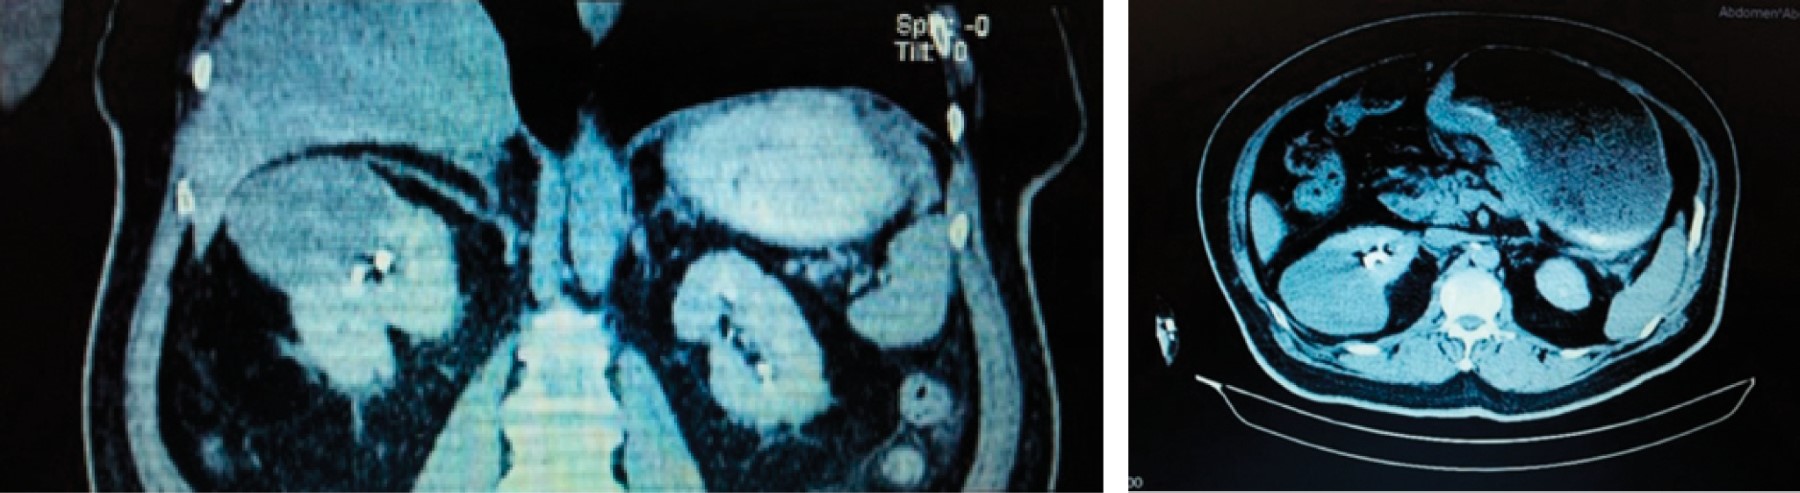

PRESENTACIóN DEL CASO

Figura 1